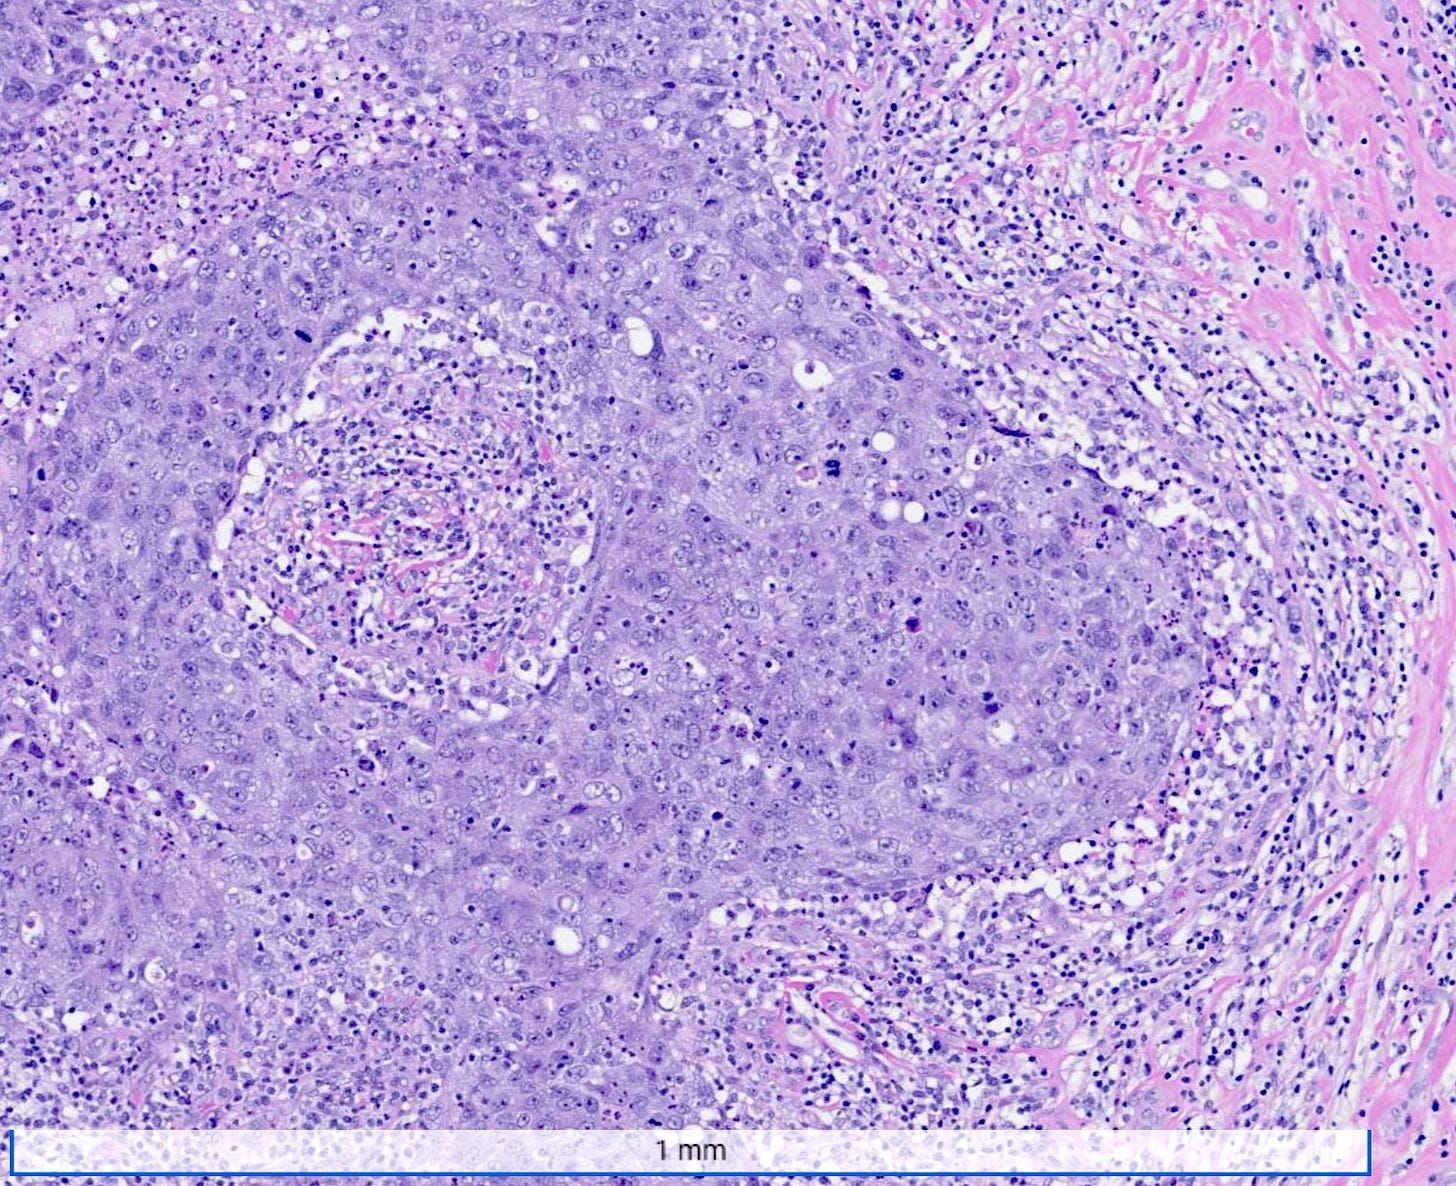

Medullary carcinoma of the breast is a rare subtype (3 - 5%) of invasive breast cancer with pushing borders, syncytial growth, high grade nuclei and a prominent lymphoid infiltrate. According to the World Health Organization, the preferred terminology is invasive breast carcinoma of no special type with medullary pattern.

Microscopically, medullary carcinoma is composed of large, pleomorphic, high grade tumor cells arranged in broad syncytial sheets occupying at least 75% of the tumor area. The tumor cells have vesicular nuclei (i.e., large, pale staining with a central clearing) with prominent nucleoli and abundant eosinophilic cytoplasm. A prominent and dense lymphoplasmacytic infiltrate surrounds and often infiltrates the tumor, suggesting a vigorous host immune response. Mitotic figures are numerous and areas of necrosis may be present.

Medullary carcinoma - radiologic and microscopic images